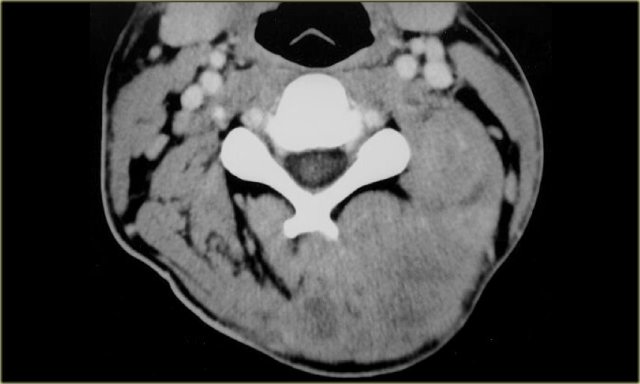

Jugular vein thrombosis

Thrombosis of the internal jugular vein is an under-diagnosed condition that may occur as a complication of head and neck infections, surgery, central venous access, and intravenous drug abuse.

An infected jugular vein thrombus caused by extension of an oropharyngeal infection is referred to as Lemierre's syndrome.

This is a bacterial infection that may have severe morbidity or even fatal outcome, as eventually septic emboli may spread to the lungs.

On the left a patient who had undergone a total laryngectomy several years previously.

The present complaint is a painful swelling on the left side of the neck since one day.

Step 1

Contrast-enhanced CT at mid-neck level shows the neopharynx with some surgical clips on the left and the enhancing right thyroid lobe which is still in situ.

In addition there is a round, hypodense lesion in the left carotid space.

Step 2

In this case, analysis of the normal anatomical contents of the carotid space can be short.

When we compare left to right it is clear that we are dealing with an internal jugular vein which is enlarged and does not enhance.

An image at a higher level shows the same appearance of the internal jugular vein (arrow).

Step 3

In combination with the clinical information of a painful swelling on the left side of the neck, there is only one possible diagnosis:

Acute thrombosis of the left internal jugular vein.

Lemierre' s syndrome

When you diagnose an acute thrombosis of the internal jugular vein, always look for pulmonary symptoms, i.e. Lemierre' s syndrome.

The oral infection spreads into the neck and causes internal jugular vein thrombophlebitis with subsequent septic emboli.